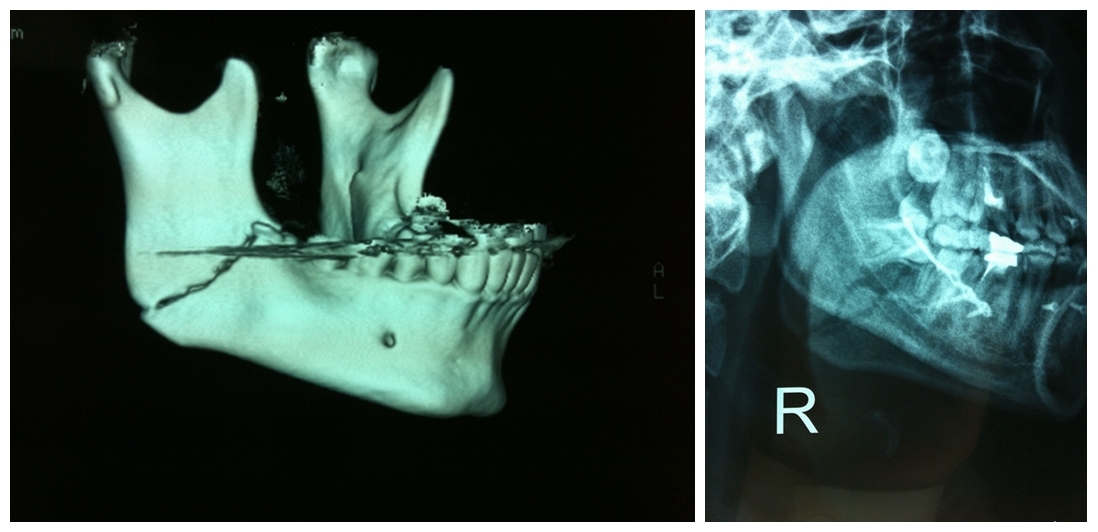

頜面部骨折導(dǎo)致的面容及咬合關(guān)系的改變

BO理論:不必過分強(qiáng)調(diào)解剖復(fù)位,更多著重咬合功能的恢復(fù)

堅(jiān)強(qiáng)內(nèi)固定聯(lián)合變化的頜間牽引保證術(shù)中以及術(shù)后咬頜關(guān)系的恢復(fù)